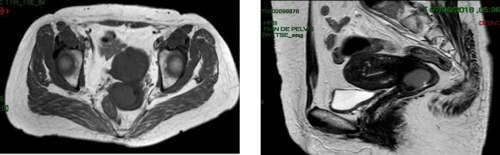

Se realizó tomografía computada de pelvis donde se observó vejiga distendida de paredes delgadas sin lesiones intraluminales. Útero en antero versión, lateralizado a la izquierda, el cérvix prominente con formación endoexofítica con realce postcontraste endovenoso que asocia cambios en la densidad de la grasa para cervical con la presencia de bandas lineales hiperatenuantes, impronta la vejiga con extensión hasta los márgenes de la vagina con aparente plano de transición con estas estructuras, mide 66x67mm (tx sp), adenomegalias iliaca internas y obturatrices con tamaño de hasta 10x17mm, en la región anexial derecha formación quística redondeada de 34x37mm. Ampolla rectal de características normales. Se concluye el estudio como formación cervical sólida endo-exofítica en relación a primario conocido con datos de compromiso de los parametrios que incluyen adenomegalias regionales, sin hallazgos de compromiso a distancia (Figura 4).

Útero en antero versión, lateralizado a la izquierda, el cérvix prominente con formación endoexofítica con realce postcontraste endovenoso que asocia cambios en la densidad de la grasa para cervical con la presencia de bandas lineales hiperatenuantes, impronta la vejiga con extensión hasta los márgenes de la vagina con aparente plano de transición con estas estructuras